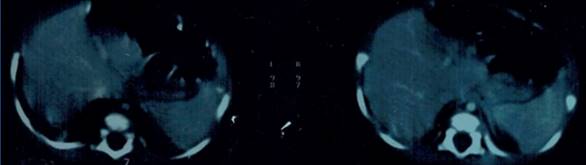

Se solicitó una TC de tórax (Figura 2), que se realizó 4 días después del ingreso, cuando la situación clínica era favorable, sin síndrome funcional respiratorio. Este estudio informó la presencia de una voluminosa imagen quística en tercio medio e inferior de hemitórax derecho, de 64 x 40 x 45 mm, que podría corresponder a una MVAP. No se constataron otras malformaciones.

Figura 2: Tomografía computada de tórax.